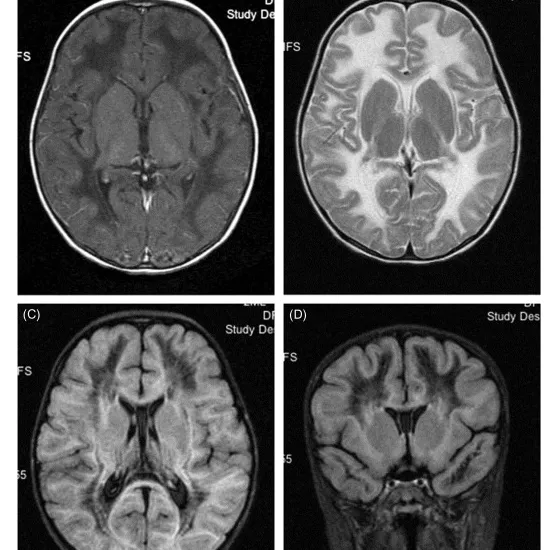

An MRI could be used to examine your brain. MLD causes sulfatide build up in the brain. An MRI can reveal this.